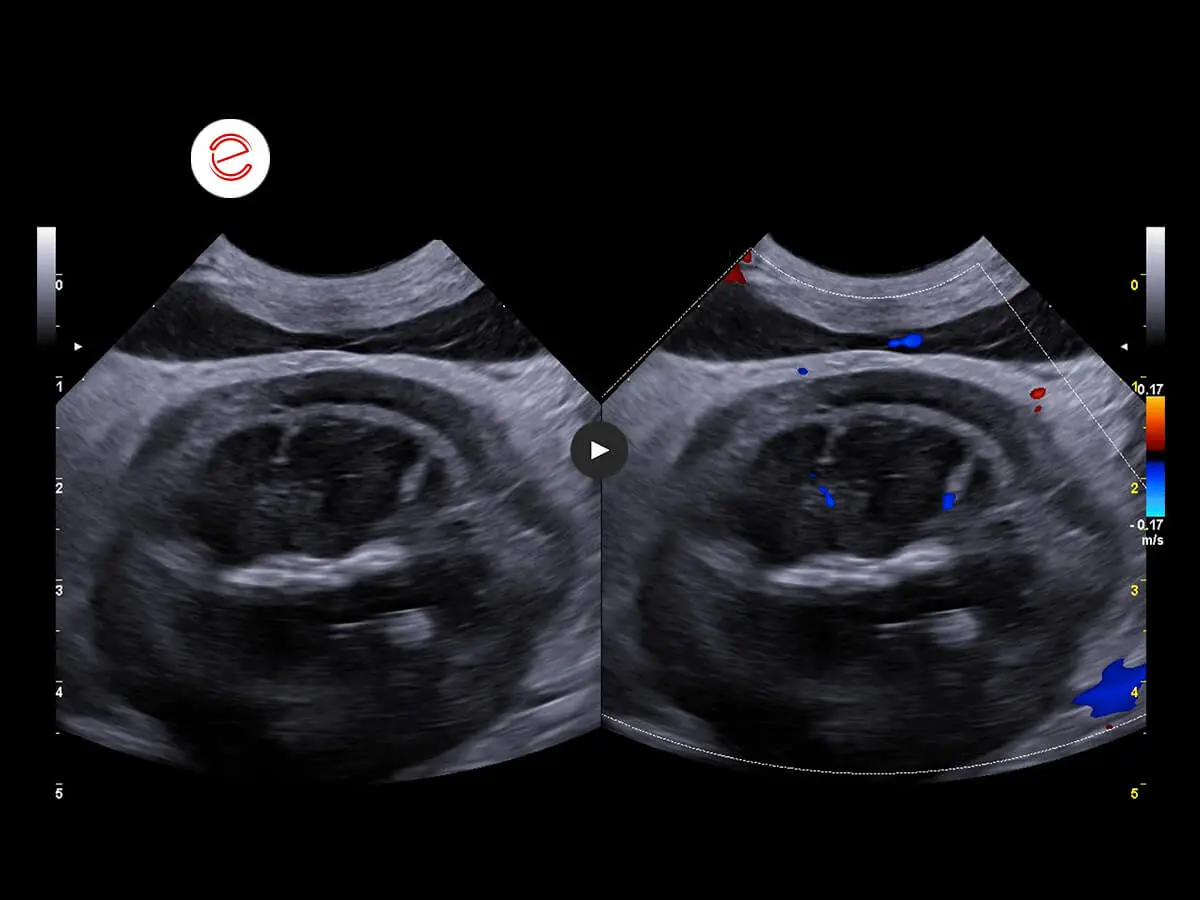

Vascularization of the right kidney preserved.

The alterations in the right kidney are compatible with a neoplastic infiltrative process in a differential diagnosis with hydronephrosis secondary to a severe inflammatory process. Alterations in the left kidney consistent with severe nephropathy associated with findings of calcifications in differential diagnosis with lithiasis. Diffuse peritonitis also observed. Cytological examination of the right kidney recommended.